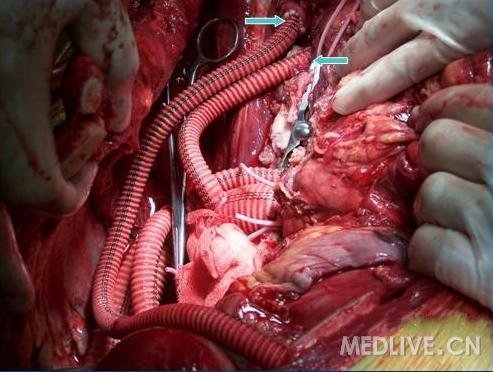

图6  双侧颈动脉搭桥,弓部分支起始结扎。右颈动脉和人造血管端侧吻合,左颈总和人工血管端端吻合

http://group.medlive.cn/webres/upload/000/055/402